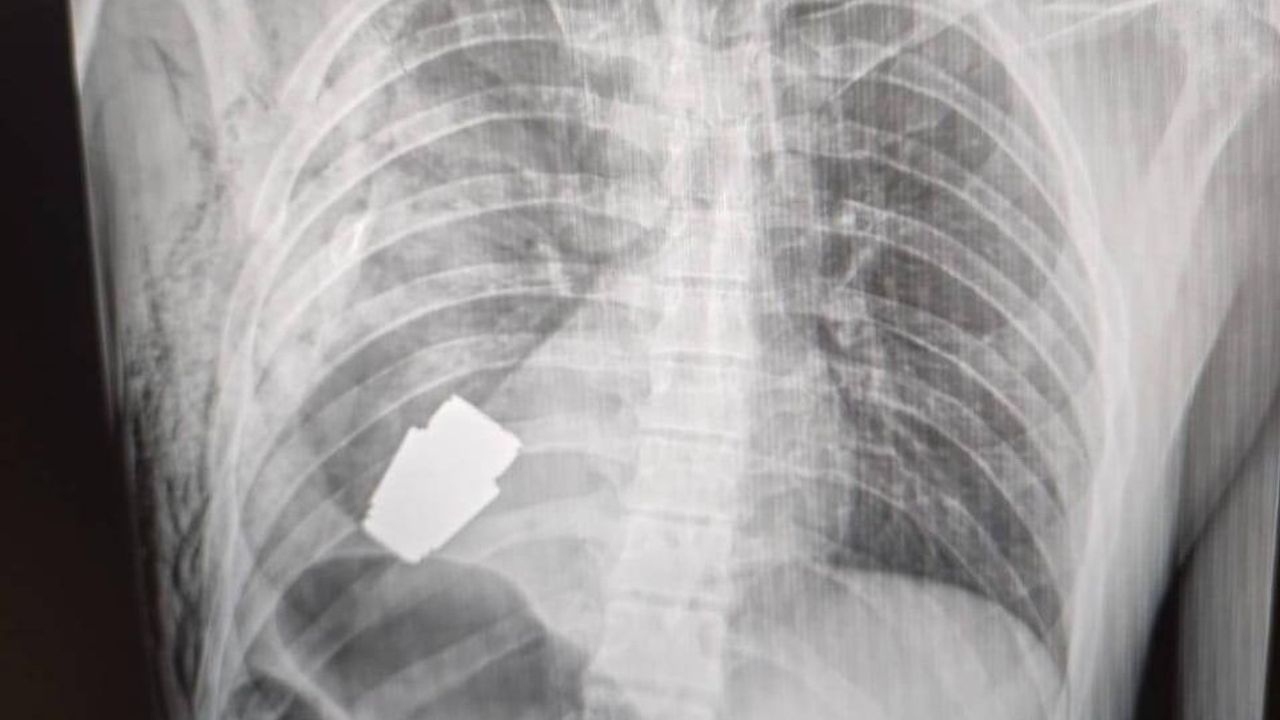

Ukrayna'da bir askerin kalbine yakın bölgesinde VOG el bombası tespit edilmesinin ardından gerçekleştirilen ameliyat sonucu patlayıcı başarılı bir şekilde çıkarıldı.

Ukrayna'da bir askerin kalbine yakın bölgesinde patlamamış VOG el bombası tespit edildi.

Bombanın her an patlayabilme ihtimali olduğu için Ukrayna Silahlı Kuvvetlerinin en deneyimli cerrahlarından biri olan Andrii Verba tarafından acil bir operasyon gerçekleştirildi. Ukrayna Savunma Bakanı Yardımcısı Hanna Maliar, cerrahi müdahalenin başarılı olduğunu ve askerin tedavi altına alındığını söyledi.